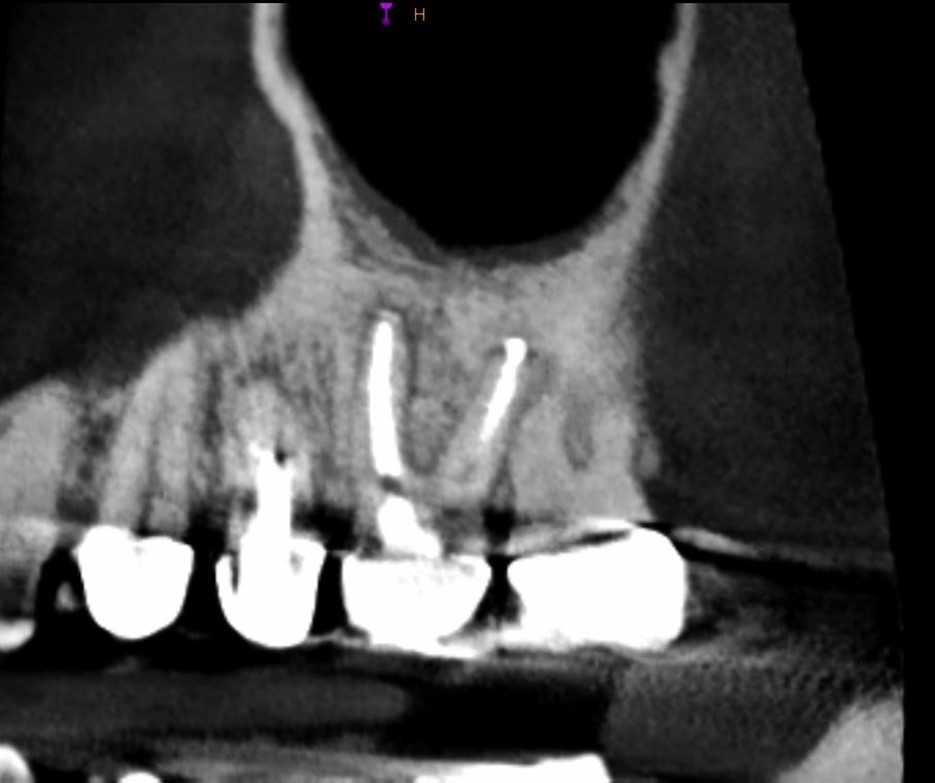

Accurate diagnosis is sometimes the most difficult aspect of daily clinical practice. CBCT has improved the trained practitioner's ability to find hidden periapical pathology, particularly in areas where structures such as the maxillary sinus and zygomatic arch, as well as thick cortical bone, can conceal periradicular lesions (Figure 7 and Figure 8).5-7

Fig 7. 2D radiograph of tooth No. 3.

Figure 7

Fig 8. 3D CBCT image of tooth No. 3 revealing hidden periapical pathology.

Figure 8